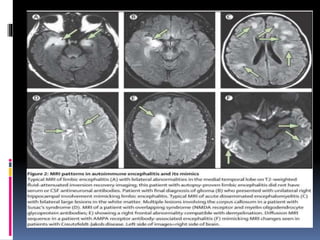

 MRI demonstrate medial temporal lobe

attenuated inversion recovery high signal or

focal areas of hyperintensity in the frontal or

parietal cortex

 MRI – often shows increased signal onT2w FLAIR in the medial aspect of the

temporal lobes.